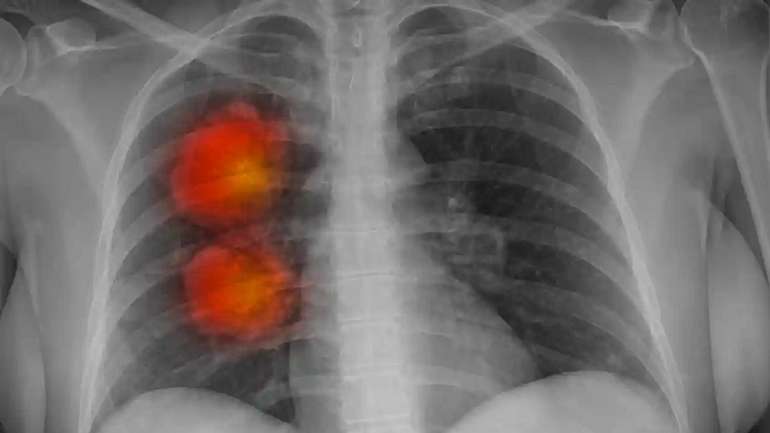

Штучний інтелект навчився ідентифікувати рак на ранніх стадіях

Британські лікарі та науковці створили модель штучного інтелекту, яка з високою точністю визначає злоякісну пухлину з епітеліальної тканини.

За словами учасників проєкту, винайдена інноваційна технологія має змогу прискорити діагностику захворювання та лікування пацієнтів із різними стадіями раку.

«Ми використали комп'ютерну томографію близько 500 пацієнтів із великими вузлами у легенях для розробки алгоритму, який може отримувати важливу інформацію із медичних зображень. Коли модель штучного інтелекту протестували, вона виявилася більш ефективною та дієвою, ніж інші існуючі методи.

Сподіваємося, що у майбутньому це покращить раннє виявлення пухлин і потенційно зробить його лікування успішнішим, особливо шляхом виявлення пацієнтів із високим ризиком. Цілком очевидно, що наша технологія допоможе лікарям швидше приймати рішення про пацієнтів з аномальними новоутвореннями», – повідомили британські науковці.